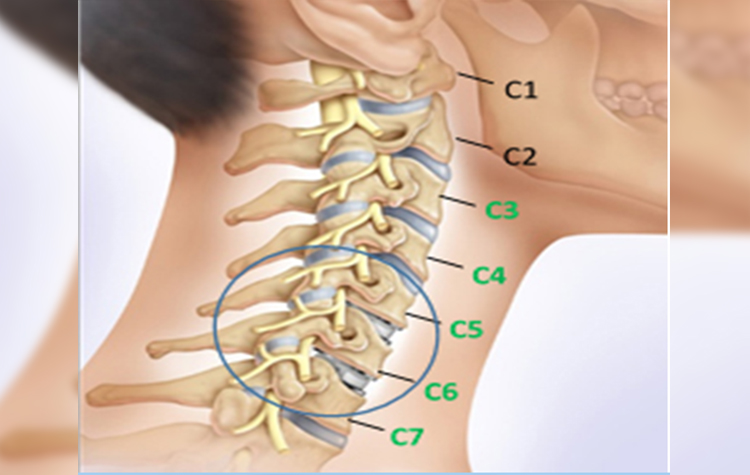

КТ-протрузии дисков: Визуализация и классификация